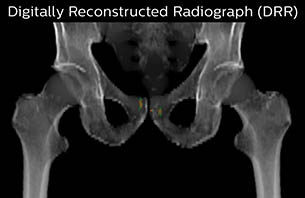

Using the mDIXON and 3D bFFE images, the RT planner marks the position of the nickel-titanium fiducial markers, and contours are transferred to the digitally reconstructed radiographs (DRRs). Reference image matching is based on these markers. “In the rare cases, where visualization of the fiducial markers fails, we do a CT to confirm their location,” Dr. Keyriläinen notes.

Turku MR-RT Digitally Reconstructed Radiograph case 6

The 3D T1W FFE mDIXON sequence provides in-phase, water and fat images in one acquisition. Target and organs-at-risk are delineated on the 3D T2W TSE images. Prostate GTV is shown in orange, PTV in purple. The 3D bFFE sequence is used by the planner to mark the position of the fiducial markers (gold anchors) and contours are transferred to the digitally reconstructed radiographs (DRRs).

Based on the 3D T1W mDIXON images, MR-based density maps (MRCAT) are automatically generated. The VMAT (Volumetric Modulated Arc Therapy) plan is generated in TPS, based on MRCAT as primary image set. During the commissioning phase, dosimetric agreement between MRCAT-based and CT-based dose plans was studied and differences in the PTV dose were found to be minimal (<1% for most patients). Average difference in PTV mean values was 0.8% over the study group (n=62).